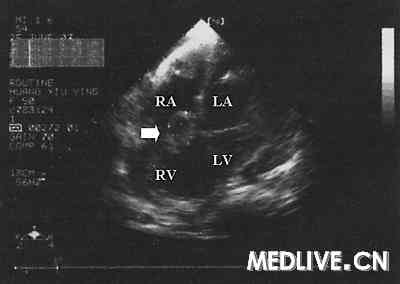

UCG示右房、右室间肿块

图2   UCG示右房、右室间肿块(↑)提示肿瘤心腔内转移。RA=右房,RV=右室,LA=左房,LV=左室